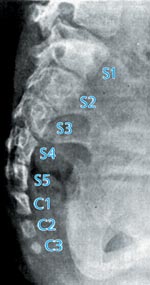

Abb. 9: Schematische Anatomie der Wirbelsäule und des Steißbeins. (Nach Fenis 1988)

Der Schwanz ist ein charakteristisches Merkmal nahezu aller Organismen, die zu den Wirbeltieren (Vertebraten) zählen. Damit unterscheiden sie sich u.a. von den übrigen Unterstämmen der Chordata (Tiere mit Anlage einer Chorda dorsalis), zu denen z.B. die Tunicaten (Manteltiere) und das Lanzettfischchen (Amphioxus) zählen. Bei ausgewachsenen Wirbeltieren läßt sich ein allgemeiner Bauplan des Schwanzes wie folgt beschreiben (nach Romer & Parsons [1991], vgl. dazu Abb. 6). Im Querschnitt zeigt dieser typischerweise ein aufrecht stehendes Oval, zentral gelegen ist die Wirbelsäule – speziell die Elemente des Steißbeins (Os coccygis) –, darüber angeordnet ist das Neuralrohr, in dem Nerven, Anteile des Rückenmarks oder nur die Rückenmarksflüssigkeit zu finden sind. Jegliche Andeutung einer Art Leibeshöhle mit den von ihr umschlossenen Eingeweiden fehlt. Weiterhin zur Grundstruktur gehören segmental angeordnete Muskelgruppen und unterhalb der Wirbelkörper verlaufende Blutgefäße. Bei den Wirbeltieren besteht eine große Variabilität bezüglich der Anzahl der Wirbelkörper (30-200), bei den meisten Säugetierordnungen hingegen ist bis auf die Schwanzregion (0-50 coccygeale Wirbelkörper) die Anzahl der übrigen Wirbelkörper im Bereich der Hals-, Brust-, Lendenwirbelsäule und des Kreuzbeins relativ konstant.